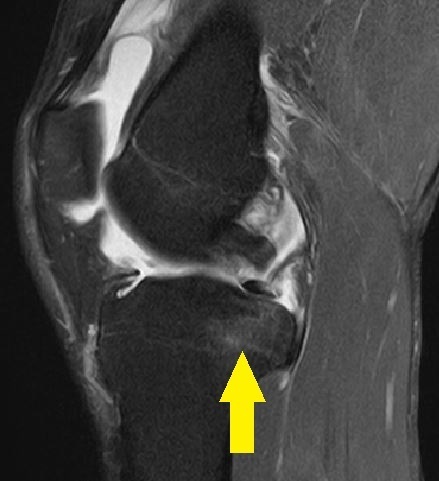

MRI画像①

大腿骨内顆・外顆に骨挫傷

②

脛骨後顆に骨挫傷

③

前十字靭帯が不明瞭